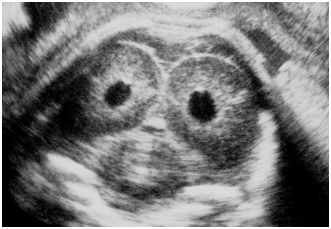

Yamamoto et al.8 studied fetal brain in preterm pregnancy detecting periventricular echodensity (PVE) (Figure 5), of which 18 % (corresponding 0.2 % of all births) preceded neonatal periventricular leukomalacia (PVL) followed by cerebral palsy (CP), if the PVE lasted until preterm birth, while there was no neonatal PVL when the PVE disappeared before birth. Also, no PVE developed in full-term births’ neonates. The GLHW of fetal PVE was 36±5 % which was significantly larger than 23±5 % of normal fetal brain GLHW,8 thus, GLHW is useful to diagnose fetal and neonatal brain PVE in the prevention of neonatal PVL and CP, namely, the PVE ultrasonically detected immediately after a preterm birth will be effectively treated administrating medicines, e.g. growth factor, erythropoietin, hydrocortisone etc, in the future.

Figure 5 A case of fetal brain PVE, which was white tissues around fetal ventricles in ultrasound B-mode image. It persisted until preterm birth in the case then changed to periventricular leukomalacia, followed by cerebral palsy.